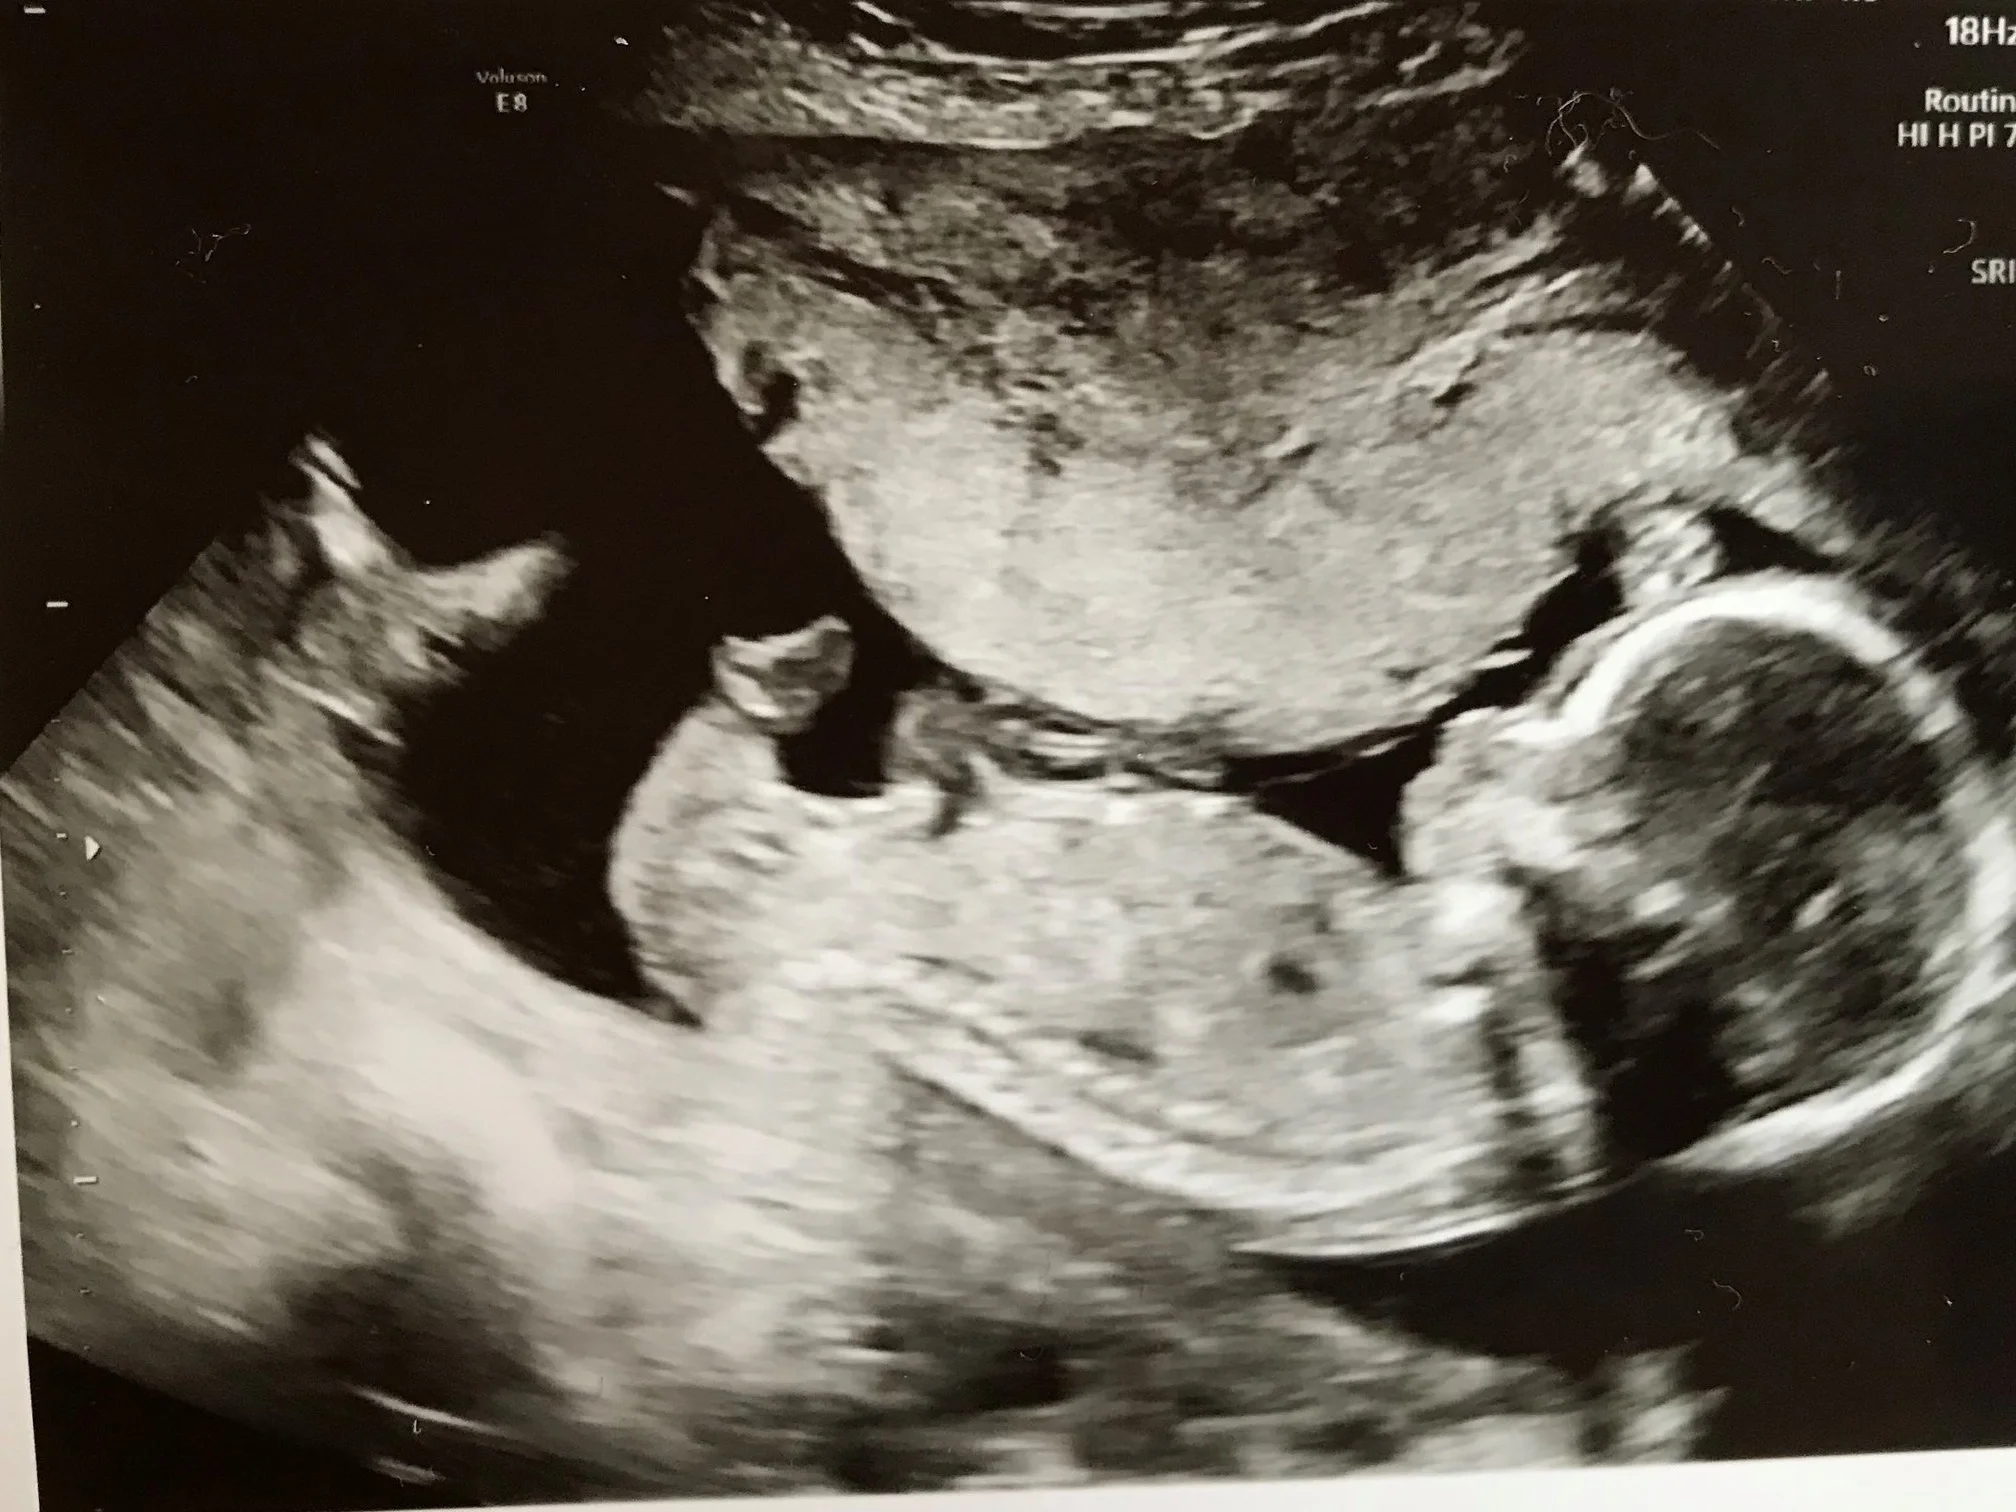

Overcoming Fear Infertility, Health & Fitness, FamilyErin KiernanDecember 15, 2017infertility, fear, anxiety, pregnancy, family